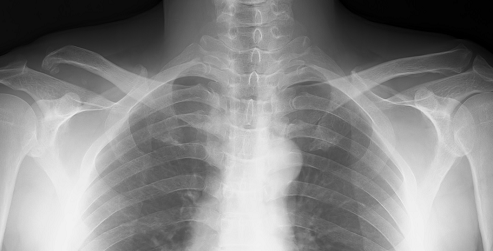

当院にこられた際のレントゲンです。